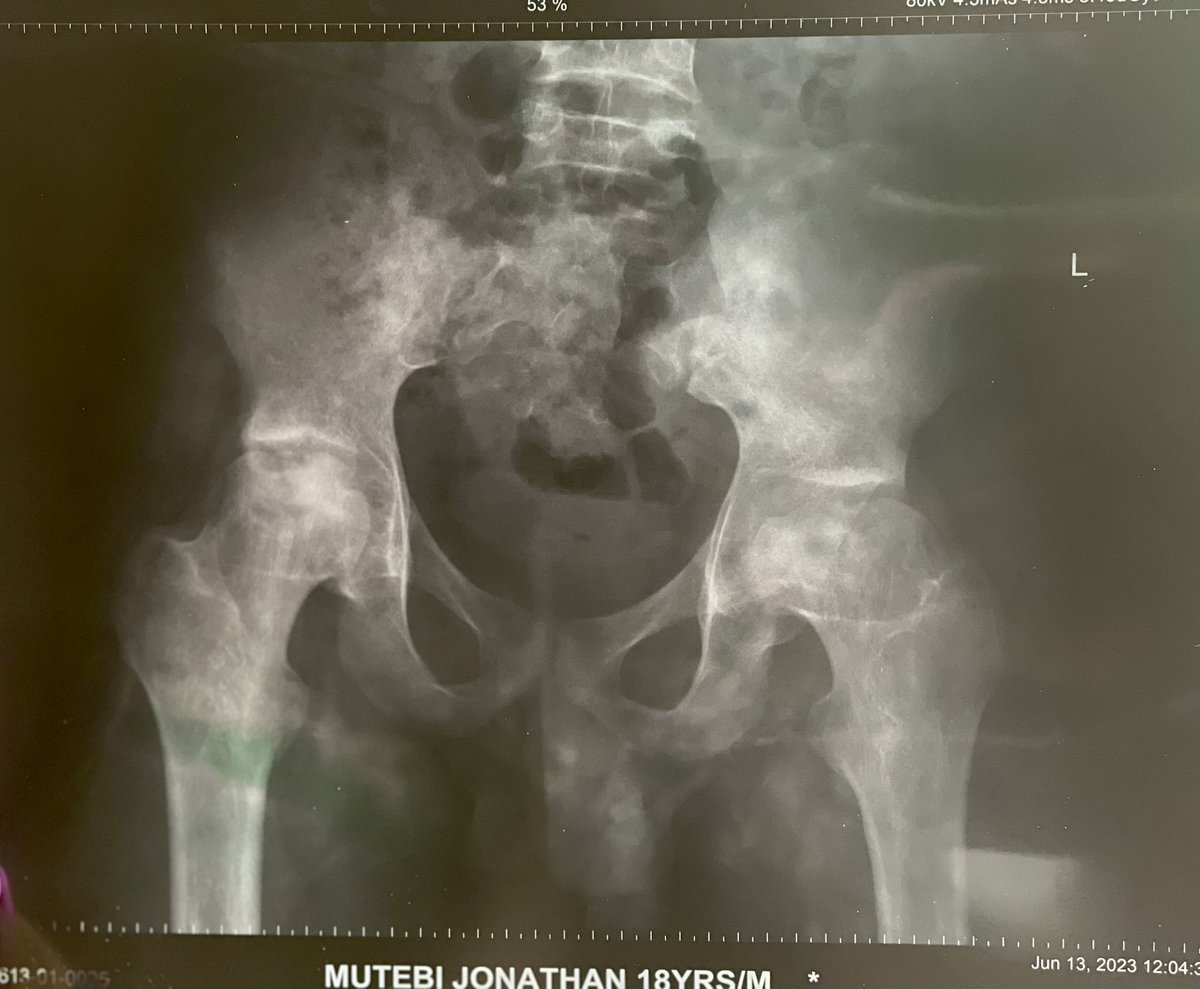

Greetings, my name is Dr. Angel Lisa Nansubuga and I would like to introduce to you the cause for my brother Mutebi Jonathan Leone. Jonathan is a sickle cell warrior who has battled with crises since his birth and this has complicated his life.

Jonathan is a sickle cell warrior who has battled with crises since his birth and this has complicated his life.